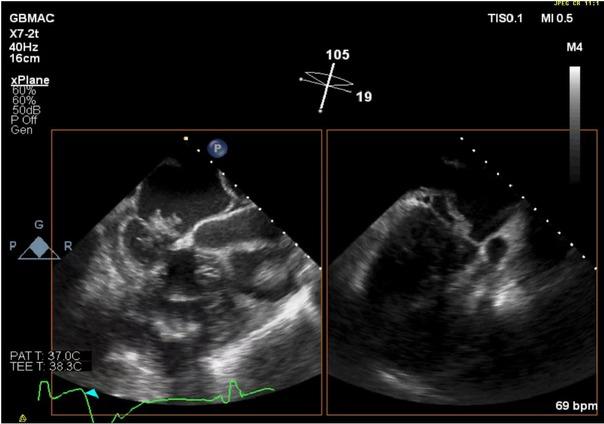

The possibility of acute myocardial infarction (MI), likely in the right coronary artery (RCA) distribution region, was considered. TEE video clips demonstrate clots located in all four chambers (Figure1; Online supplementary video 1); a massive clot in mitral position on the biplane view (Figure 2; Online supplementary video 2); and clots in both ventricles, as demonstrated on Figure 3 (Online supplementary video 3), that also showed that right ventricular outflow tract (RVOT) inflow-outflow was almost obstructed with a clot in AV.

Fig. 2

Massive clot in mitral position on the biplane view